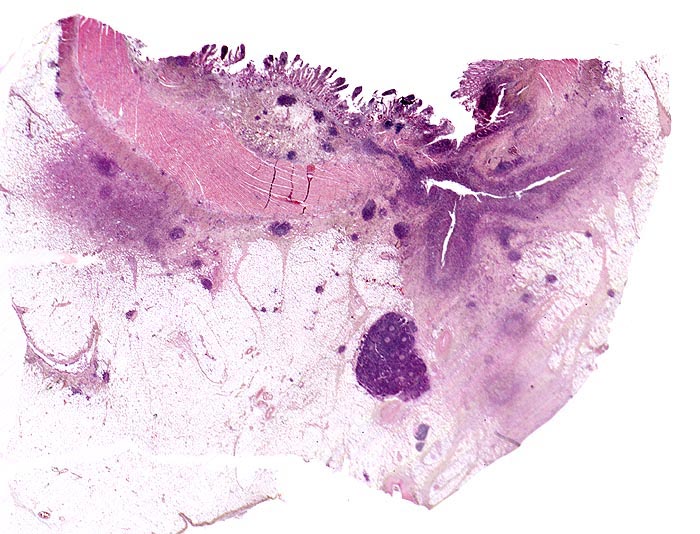

Basel 3BA HS/ Morbus Crohn

Morbus Crohn

Ileum terminal

Die Verteilung der Läsionen im Darm ist sowohl makrokopisch (> 2884) als auch mikroskopisch (> 656) (> 409) diskontinuierlich und herdförmig ausgeprägt. Im Gegensatz zur Colitis ulcerosa können beim Morbus Crohn nicht nur das Kolon, sondern sämtliche Abschnitte des Gastrointestinaltraktes befallen sein. Am häufigsten ist das terminale Ileum zusammen mit dem Kolon befallen.

Makroskopisch typisch sind oberflächliche aphthöse Ulzera, gartenschlauchartige Strikturen im Dünn- und Dickdarm mit segmental verdickter und fibrosierter Darmwand, intramurale Abszesse, entzündliche Konglomerattumoren und verbackene Darmschlingen mit Fistelbildungen. Häufiger im Dünndarm als im Dickdarm findet sich das klassiche Pflastersteinrelief der Schleimhaut aufgrund rissförmiger Ulzera zwischen ödematösen Schleimhautarealen (> 369) Granulationsgewebspolypen oder Pseudopolypen (erhaltene Schleimhautinseln in Ulkusarealen) (> 408) finden sich beim Crohn seltener als bei der Colitis ulcerosa.

In Biopsien der Darmschleimhaut zeigen sich als Zeichen der Chronizität eine Architekturstörung, reepithelialisierte Schleimhautdefekte und metaplastische Veränderungen. Typisch für den Morbus Crohn sind entzündlich veränderte Schleimhautabschnitte neben weitgehend normaler Schleimhaut. In der Lamina propria findet sich ein verdichtetes gemischtes Infiltrat bestehend aus Lymphozyten, Plasmazellen, Makrophagen, neutrophilen und eosinophilen Granulozyten. Typisch für chronisch entzündliche Darmerkrankungen ist eine basal betonte Lymphoplasmozytose der Lamina propria. Die neutrophilen Granulozyten finden sich herdförmig in der Lamina propria, im Kryptenepithel (Kryptitis) und als Ansammlung in dilatierten Krypten (Kryptenabszess). Erhaltene Schleimhautabschnitte zwischen ulzerierten Arealen und Granulationsgewebe imponieren als entzündliche Pseudopolypen.

Befunde in der Mukosa wie epitheloidzellige Granulome, aphthöse Ulzera und Erosionen und fokal aktive Entzündung sind nicht spezifisch für den Morbus Crohn. Jene histologischen Aspekte, welche die Erkrankung am besten charakterisieren, sind in der Darmwand gelegen und lassen sich an einer endoskopisch gewonnenen Biopsie nicht nachweisen (fissurale, spaltförmige Ulzera, submukosales Ödem mit Lymphangiektasien, submukosale Fibrose, transmurale Entzündung mit lymphoidzelligen Aggregaten, neuromuskuläre Hypertrophie mit Wandverdickung (> 364), subseröse und submuköse Granulome (> 1133)).

Morphologische Merkmale:

• Architekturstörung: Verplumpung und Abflachung der Dünndarmzotten. Verzweigte Krypten.

• Transmurale Entzündungsinfiltrate mit Lymphfollikelbildung.

• Zahlreiche epitheloid-riesenzellige Granulome in allen Wandschichten.

• Schlitzförmige fissurale Ulzera mit Vernarbung der umgebenden Submukosa.

• Verdichtetes lymphoplasmazelluläres Entzündungsinfiltrat in der Lamina proria.

Neutrophile Granulozyten in der Lamina propria (aktive Entzündung) und Gewebseosinophilie (vermehrte eosinophile Granulozyten in der Lamina propria).